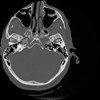

4 CEREBRO,,Vol,0.5,CEREBRO,,